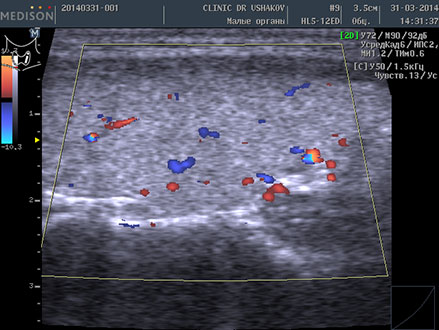

| В левой доле (в сосудистом режиме; ЦДК) заметно усиление кровотока ― свойственно избыточному напряжению железы | В левой доле (в сосудистом режиме; ЦДК) кровоток восстановился до оптимальной интенсивности ― нормальное состояние железы |